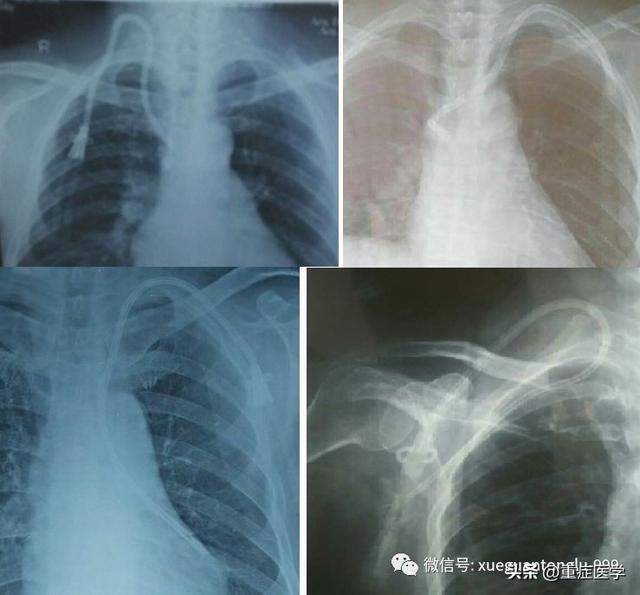

比如:右颈内静脉置管,导管尖端到达右锁骨下静脉;比如,右颈内静脉置管,导管尖端到达左无名静脉;又比如,左颈内静脉置管,导管尖端到达奇静脉……

3、关于颈内静脉穿刺导致的血肿,部分患者血肿的来源可能不是颈总动脉,而是来源于椎动脉。此外,部分肿瘤合并下腔静脉阻塞的患者,其椎静脉会代偿性的增宽,颈内静脉置管时可能会误入椎静脉(如下图所示)

4、此外,一些颈部疾病的患者,其血管会有异常变化,需要额外关注。日本宇部市中心医院麻醉科 Yasuhiro 教授等报道了 1 例超声扫描检出邻近颈内静脉的巨大甲状腺下动脉,该患者甲状腺异常肿大,麻醉科行颈内静脉置管时,超声检查发现:一大动脉贴近颈内静脉内侧(如图所示)。从直径宽度来看,该动脉与颈动脉相近,但从分支来看,该动脉起源于锁骨下动脉,继而流入甲状腺外侧。因此,考虑该动脉为甲状腺下动脉。为了避免颈内静脉置管时误伤动脉,后改行左颈内静脉置管。

16、如果颈内静脉及股静脉置管有困难,可以考虑颈外静脉置管(如下图所示)。